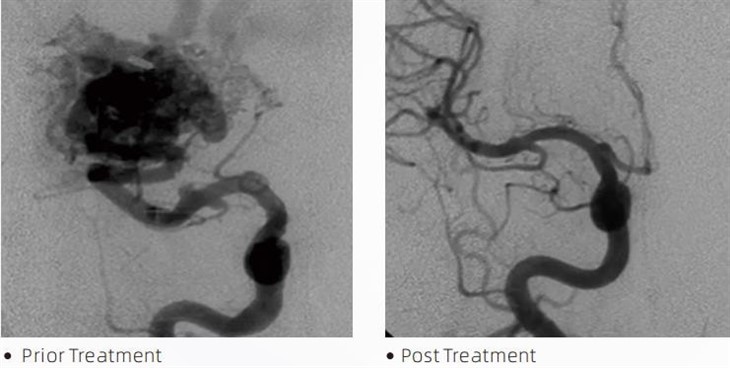

dung nhamTMkeo thuyên tắc là một thiết bị y tế được các bác sĩ thần kinh học can thiệp sử dụng trong các thủ thuật xâm lấn tối thiểu để điều trị các tình trạng như chứng phình động mạch não, dị dạng động tĩnh mạch và khối u. Keo thuyên tắc Lava mang lại nhiều lợi ích cho các chuyên gia y tế cũng như bệnh nhân về tính an toàn, dễ sử dụng và hiệu quả. Dung nham có thể bịt kín các mạch máu một cách nhanh chóng và hiệu quả. Quá trình này bao gồm việc tiêm keo trực tiếp vào mạch mục tiêu, tại đây keo trùng hợp và cứng lại thành một khối giống như khuôn đúc lấp đầy chỗ phình động mạch hoặc dị tật. Sau đó, nó sẽ cắt đứt dòng máu đến tổn thương một cách hiệu quả, ngăn ngừa tổn thương bị vỡ và giảm nguy cơ tổn thương vĩnh viễn hoặc đột quỵ. Dung nham bao gồm Dung nham-12, Dung nham-18 và Dung nham-34. Mỗi công thức được thiết kế để đáp ứng nhu cầu lâm sàng cụ thể. Lava-18 là công thức tiêu chuẩn để sử dụng chung. Lava-34 là loại keo có độ nhớt cao dành cho bình có lưu lượng lớn. Trong khi Lava-12 có độ nhớt thấp hơn và dễ chảy hơn, cho phép các vi mạch ở xa. Với các tùy chọn này, các nhà thần kinh học can thiệp có thể chọn các công thức Lava phù hợp để đảm bảo kết quả tối ưu. Một trong những tính năng đáng chú ý nhất của Lava là đặc tính không kết dính của nó. Chất này được pha chế đặc biệt để duy trì sự ổn định cho đến khi đến được khu vực mục tiêu. Đặc điểm này có nghĩa là keo thuyên tắc Lava có thể được đặt chính xác trong động mạch và ở yên đó mà không dính hoặc dính vào các mô xung quanh.